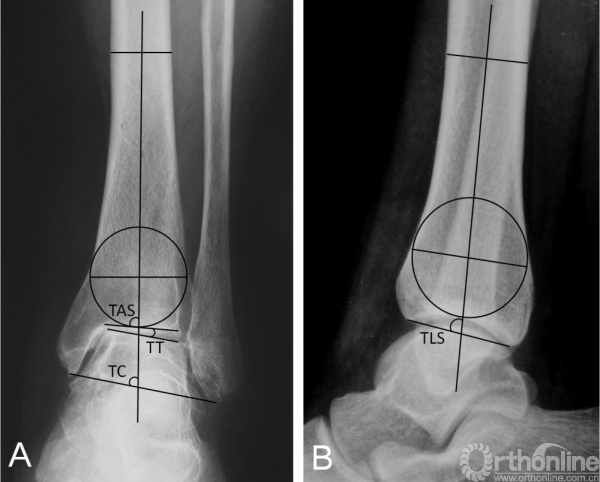

方法 回顾性分析2009年4月-2014年4月通过踝上截骨治疗内翻型踝关节炎并随访至少1年的41例患者资料,男14例,女27例;平均年龄50.7岁(32~71岁);根据改良Takakura踝关节炎分期,2期14例,3a期19例,3b期8例;共19例保留腓骨,22例行腓骨截骨。通过美国足踝骨科协会(American orthopedic foot and ankle society,AOFAS)踝与后足评分、Maryland足部评分踝关节骨关节炎量表(Ankle OsteoarthritisScale,AOS)进行临床评估,并测量比较踝关节活动度(Rangeof Motion,ROM)。影像学测量内容包括胫骨前侧关节面角(tibial anterior surface angle,TAS)、距骨倾斜角(talar tilt angle,TT)、胫骨踝穴角(tibiocrural angle,TC)以及胫骨侧位关节面角(tibial lateral surface angle ,TLS)。

临床评估内容包括术前及末次随访的美国足踝骨科协会(Americanorthopedic foot and ankle society,AOFAS)踝与后足评分、Maryland足部评分踝关节骨关节炎量表(Ankle OsteoarthritisScale,AOS)进行临床评估,并测量比较踝关节活动度(Range of Motion,ROM)。为了便于量化统计,将改良Takakura分期的2、3A、3B及4期分别赋值为2、3、4、5。影像学测量内容包括胫骨前侧关节面角(tibial anterior surface angle,TAS)、距骨倾斜角(talar tilt angle,TT)、胫骨踝穴角(tibiocrural angle,TC)以及胫骨侧位关节面角(tibial lateral surface angle ,TLS)(图1)。

图1 踝关节前后位X线片(1A): TAS,胫骨前侧关节面角;TT,距骨倾斜角;TC,胫骨踝穴角。踝关节侧位X线片(1B):TLS胫骨侧位关节面角。